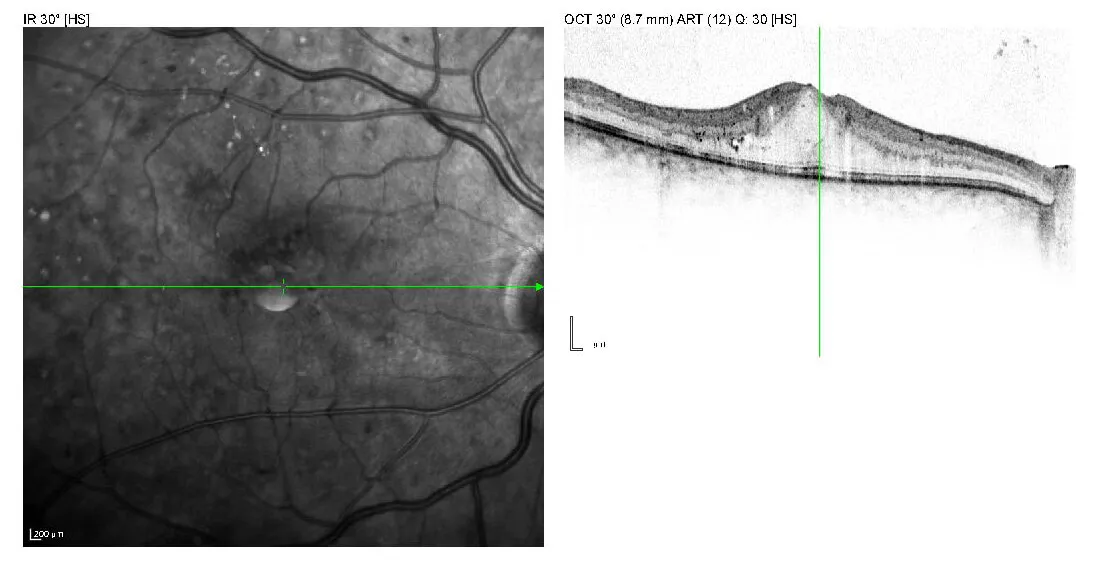

- Diabetische Makulopathie: die undichten Gefäße führen zur Flüssigkeitsansammlung an der Makula (Makulaödem) und damit zur Sehverschlechterung.

Damit es nicht so weit kommt, sollten vordergründig die Blutzuckereinstellung und der Blutdruck überprüft und ggf. optimiert werden. Der Augenarzt empfiehlt in bestimmten Stadien der Erkrankung Zusatzdiagnostik wie die Fluoreszenzangiografie oder das OCT, welche Aufschluss über die Schwere der diabetischen Veränderungen und Behandlungsbedarf geben.

- Das diabetische Makulaödem wird mit wiederholten Injektionen ins Auge (IVOM) behandelt. Ziel ist es, die Flüssigkeit aus der Netzhaut zu verdrängen, um eine weitere chronische Verschlechterung zu verhindern. Wenn die Durchblutung der Makula noch intakt ist, kann sich die Sehschärfe durch die Behandlung wieder erholen. In manchen Fällen ist ergänzend eine Laserbehandlung in der Nähe der Makula sinnvoll, insbesondere wenn das Ödem die Netzhautmitte noch nicht erreicht hat.